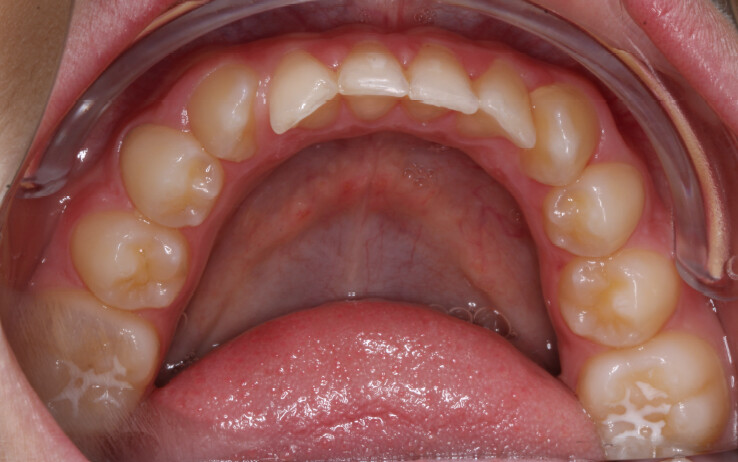

Um paciente do sexo masculino, com 13 anos de idade, apresentou-se com uma mordida profunda, caracterizada pela cobertura quase completa dos incisivos mandibulares. A avaliação clínica revelou apinhamento em ambas as arcadas, rotações dentárias e proclinação dos incisivos laterais superiores, contribuindo para as preocupações estéticas do paciente. O perfil facial era retrusivo, consistente com retrognatismo mandibular, e não foram detectadas anomalias periodontais significativas.

O paciente apresentava uma relação esquelética de Classe II com molares e caninos bilaterais em Classe II e um padrão dentário de Classe II divisão 2. A mordida profunda estava associada a um apinhamento anteroinferior e a uma curva de Spee acentuada. A análise facial revelou boa simetria, um terço facial inferior ligeiramente aumentado e um perfil convexo caracterizado por retrusão mandibular e do mento. A competência labial estava ligeiramente reduzida, com diminuição do ângulo nasolabial e leve tensão do músculo mentoniano, fatores que comprometiam a harmonia facial global.

- Redução interproximal seletiva na região anterior mandibular para criar espaço e controlar a inclinação dos incisivos;

- Intrusão dos incisivos e caninos mandibulares para nivelar a Curva de Spee;